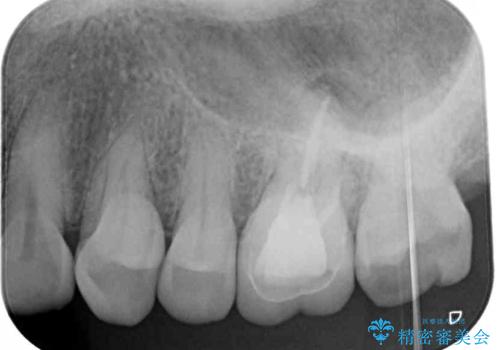

- 奥歯に装着したクラウンの周りに汚れが溜まりやすいとのことで来院された患者様です。

既に装着されているクラウンの質は決して悪いものではありませんでしたが、患者様自身が非常に気にしていたため、作り替えの治療を行うこととしました。

根管治療が必要と思えるような所見も認められませんでしたが、一緒に行いたいとの希望があったため、根管治療を行った上で補綴治療を行うこととしました。